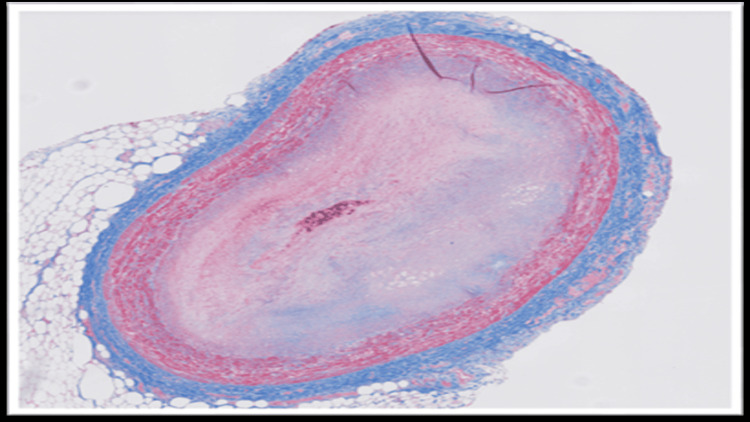

The blood and vitreous fluid were collected for toxicology analysis. Microscopic examination of the heart showed a complete occlusion (100%) of the proximal portion of the left anterior descending coronary artery due to an organized thrombus (Figure 1). A trichrome stain was performed, which showed fibroblastic growth within the thrombus (Figure 2). Elastic stain performed on the section revealed a focus of disruption of the internal elastic lamina (Figure 3). The rest of the anterior descending coronary artery, the left circumflex artery, and the right coronary artery showed normal caliber with no evidence of thrombus or atherosclerosis. A focal area of scarring was identified in the interventricular septum and left ventricle. The right ventricular wall showed a subendocardial scar. No evidence of acute myocardial infarction (e.g., myocyte necrosis, contraction band necrosis, wavy fibers, or early neutrophilic infiltration) was identified in the sections from the right and left ventricles. The abdominal aorta showed no atherosclerotic changes. Sections from the liver showed moderate macrovesicular steatosis. No fibrosis was identified.

In fatal cases of non-atherosclerotic coronary thrombosis, the diagnosis is established primarily through autopsy and postmortem toxicology analysis. Gross examination may not reveal significant atherosclerosis in these cases. Histopathological examination of the coronaries may reveal occlusion of the artery by thrombus. However, the possibility of a postmortem thrombus can be ruled out in such cases by doing ancillary studies like trichrome stain, which confirms fibroblast growth within the thrombus, and elastin stain, which reveals disruption of the internal elastic lamina, thereby favoring antemortem thrombus development. These histopathological findings, along with elevated levels of THC and its metabolites, can help in ruling out other causes of SCD, such as vasculitis or atherosclerosis, and thereby identifying the cause of death.